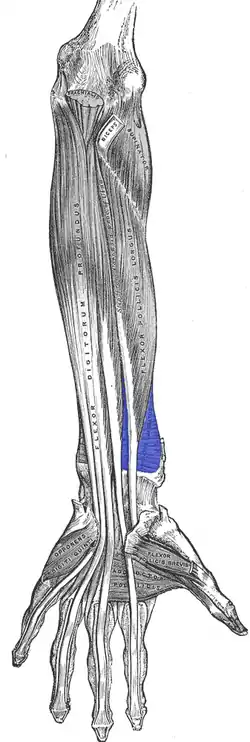

Anterior view of left forearm. Deep muscles. (Pronator quadratus visible at bottom-center right.) | |

Pronator quadratus is a square-shaped muscle on the distal forearm that acts to pronate (turn so the palm faces downwards) the hand.

Its fibres run perpendicular to the direction of the arm, running from the most distal quarter of the anterior ulna to the distal quarter of the radius. It has two heads: the superficial head originates from the anterior distal aspect of the diaphysis (shaft) of the ulna and inserts into the anterior distal diaphysis of the radius, as well as its anterior metaphysis. The deep head has the same origin, but inserts proximal to the ulnar notch.[1] It is the only muscle that attaches only to the ulna at one end and the radius at the other end. Arterial blood comes via the anterior interosseous artery.